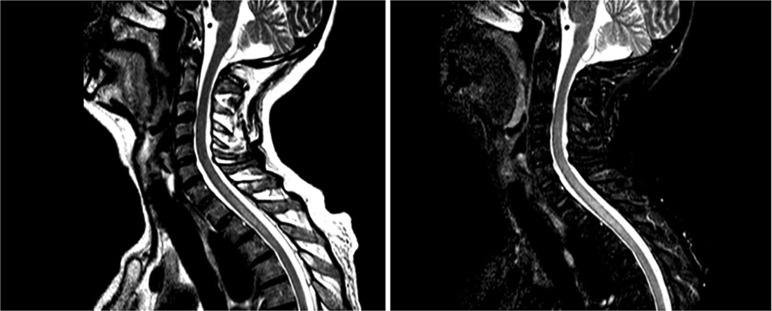

Case presentation: We describe a 54-year-old male with high-grade clear cell renal carcinoma treated with nivolumab and ipilimumab. After four cycles, he developed hypophysitis, adrenal insufficiency, and hypothyroidism, managed with hydrocortisone and levothyroxine, while continuing nivolumab monotherapy. In August 2022, he experienced right eyelid ptosis and right hand weakness. Cranial magnetic resonance imaging (MRI) showed improvement in the sellar lesion, and chronic sensorimotor polyneuropathy was diagnosed, ruling out myasthenia gravis. Nivolumab treatment continued. By December 2022, after seven cycles, the patient developed back pain and dysesthesias, with MRI confirming transverse myelitis from C7 to T3. Nivolumab was discontinued, and high-dose corticosteroids (1 g methylprednisolone daily for 5 days) led to clinical improvement. A 12-week taper followed, with no symptom recurrence. Disease progression in April 2023 led to a switch to pazopanib, maintaining a partial response for 6 months.